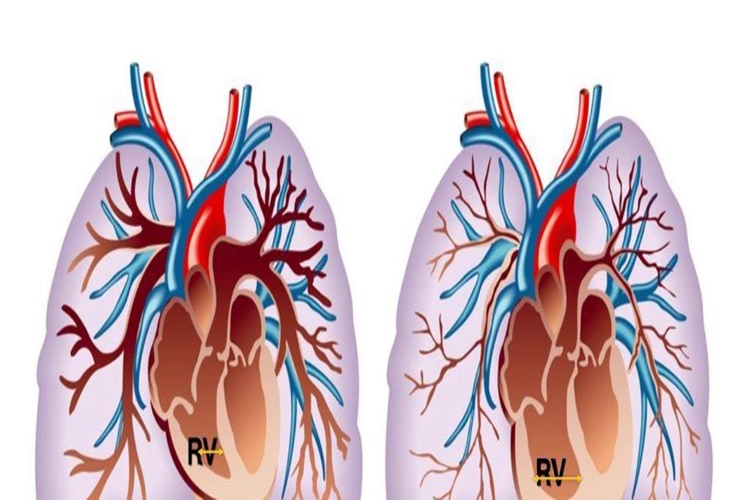

Koah Hastası Uçağa Binebilir Mi?

Evet, koah hastaları uçağa binmeyi seçebilirler ancak uçuş

şirketleri belirli koah hastalığı şartları olabileceğinden hastanın durumunu ve

gereken önlemleri kontrol etmeleri gerekmektedir. Ayrıca hastalıklarının

seyrini ve uçuş sırasında potansiyel tehlikeleri anlamak için doktorları ile de

konuşmaları önerilir.